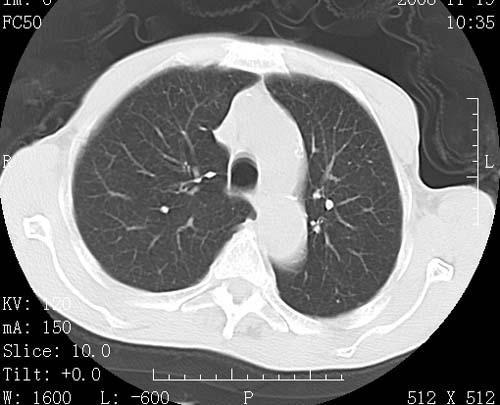

术前查体,双肺部结节是转移?结核?请点评

1)符合食管癌表现。2)两肺及纵隔淋巴结多发性转移瘤。3)左肺上叶舌段及两肺下叶炎症感染。

食管癌伴双肺转移,评述:肺部毛细血管网丰富,全身血液均快速流经肺部,癌细胞容易过滤定植,形成转移瘤,影象特点为以毛细血管末梢为中心的结节灶,边缘光滑锐利,少见有中心空洞着,不同来源的转移瘤可有各自特点,如甲状腺癌为双肺弥漫性微结节,本例有原发灶,双肺影象灶典型,左肺舌段条带状网格样伴胸膜天幕征,可视为癌性淋巴管炎。

符合食管癌表现。两肺及纵隔淋巴结多发性转移瘤。双肺还有支扩表现.

左肺舌段有斑点钙化灶,能否说明是结核而不是转移?如果是转移将放弃手术改成化疗,如果是结核将考虑择期手术